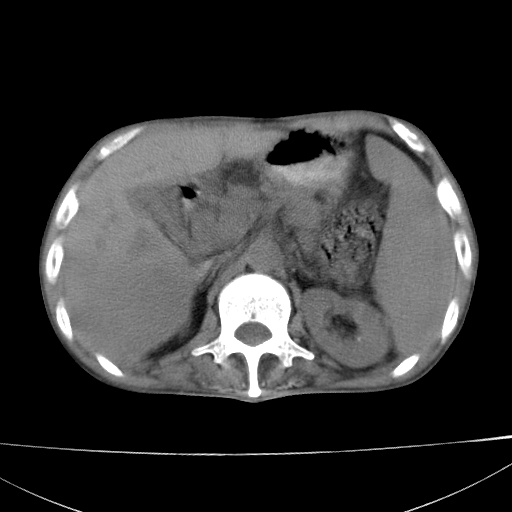

患者 男  41岁,右上腹痛伴腹泻10天,8年前有乙肝,本次b超查肝右叶占位来做ct ,请会诊!

肝硬化\\脾大\\门静脉高压,胃底静脉曲张可能性大.肝右叶肝癌肝内转移,建议增强.左侧小结石.

肝右叶肝癌肝内转移,建议增强

支持肝癌伴肝内转移,脾大,门静脉高压,胃底静脉曲张。

1)考虑肝癌;建议行ct增强扫描检查。2)脾大,门静脉高压,胃底静脉曲张。3)左肾小结石。

1)考虑肝癌及门脉瘤栓,建议行ct增强扫描检查。2)脾大,门静脉高压,胃底静脉曲张。3)左肾小结石。

结合病史;考虑肝癌。门静脉高压,脾大。胃底静脉曲张。

1)考虑肝癌;2)脾大,门静脉高压,胃底静脉曲张。3)左肾小结石。建议行ct增强扫描检查。